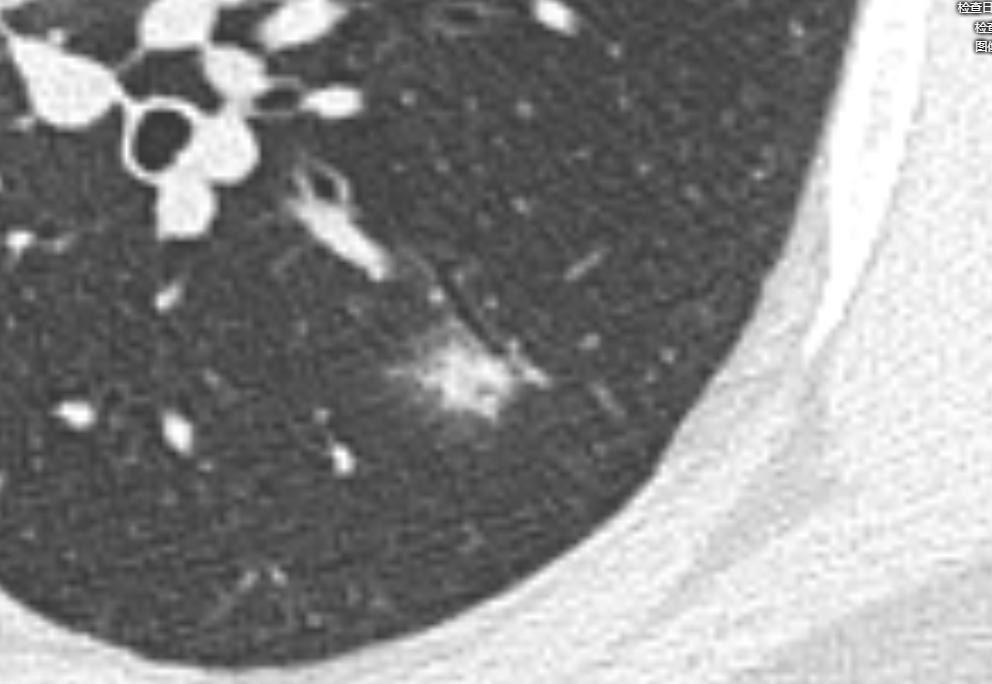

影像学是建立在高清影像的基础上的诊断,首先我们的图片要清楚,以下是患者家属提供的DICOM数据,分析时得到的图片。很多时候诊断不清楚,就是因为影像资料不清楚。

通过以上图片,病灶确实为实性结节,大小约1.0cm×0.9cm×1.0cm,呈浅分叶,周边可见毛刺,可见小血管穿入,但是影像学还是有一些不符合恶性肿瘤的特点:

1.病灶周边有一些渗出性改变。

2.相对1cm大小的肺结节来说,周边的毛刺有点长。

3.病灶及周边有扩张的支气管影。

4.病灶周边血管明显有贴边征象。